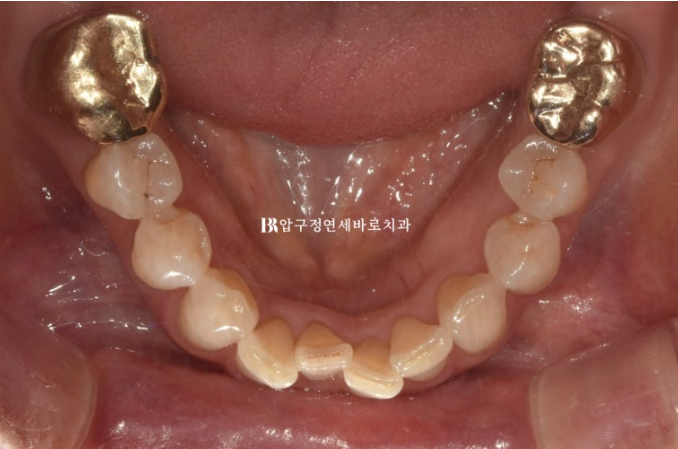

The lower teeth were also crooked.

Originally, after orthodontic treatment, only the peg lateral tooth was to have its size restored with veneers, but later it was decided to place no-prep laminate veneers on all eight front teeth.